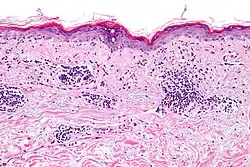

The histological hallmark of SLE is membranous glomerulonephritis with "wire loop" abnormalities.[38] This finding is due to immune complex deposition along the glomerular basement membrane, leading to a typical granular appearance in immunofluorescence testing.

Several techniques are used to detect ANAs. The most widely used is indirect immunofluorescence (IF). The pattern of fluorescence suggests the type of antibody present in the people's serum. Direct immunofluorescence can detect deposits of immunoglobulins and complement proteins in people's skin. When skin not exposed to the sun is tested, a positive direct IF (the so-called lupus band test) is evidence of systemic lupus erythematosus.[101]